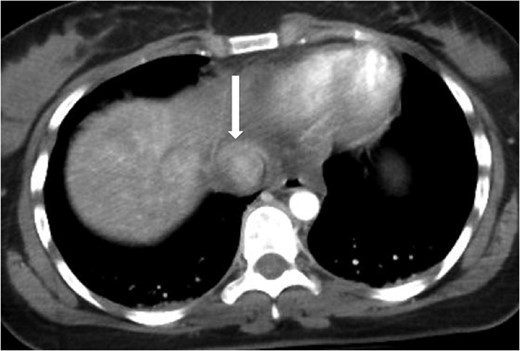

Axial contrast-enhanced CT of the chest showing abnormal contour of the supradiaphragmatic IVC with ventrally and laterally confined contrast extravasation (arrow) consistent with a pseudoaneurysm surrounded by pericaval hematoma.